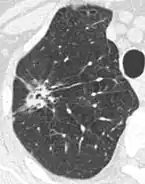

- Margin morphology: a spiculated margin is a risk factor for cancer.[8] Benign causes tend to have a well defined border, whereas lobulated lesions or those with an irregular margin extending into the neighbouring tissue tend to be malignant.[10] In particular, spiculations are highly predictive of malignancy with a positive predictive value up to 90%.[9] Also, a "notch sign", which is an abrupt indentation of the nodule, increases the risk of cancer, but may also be found in granulomatous diseases.[9]

- Spiculated lung nodule.[9]